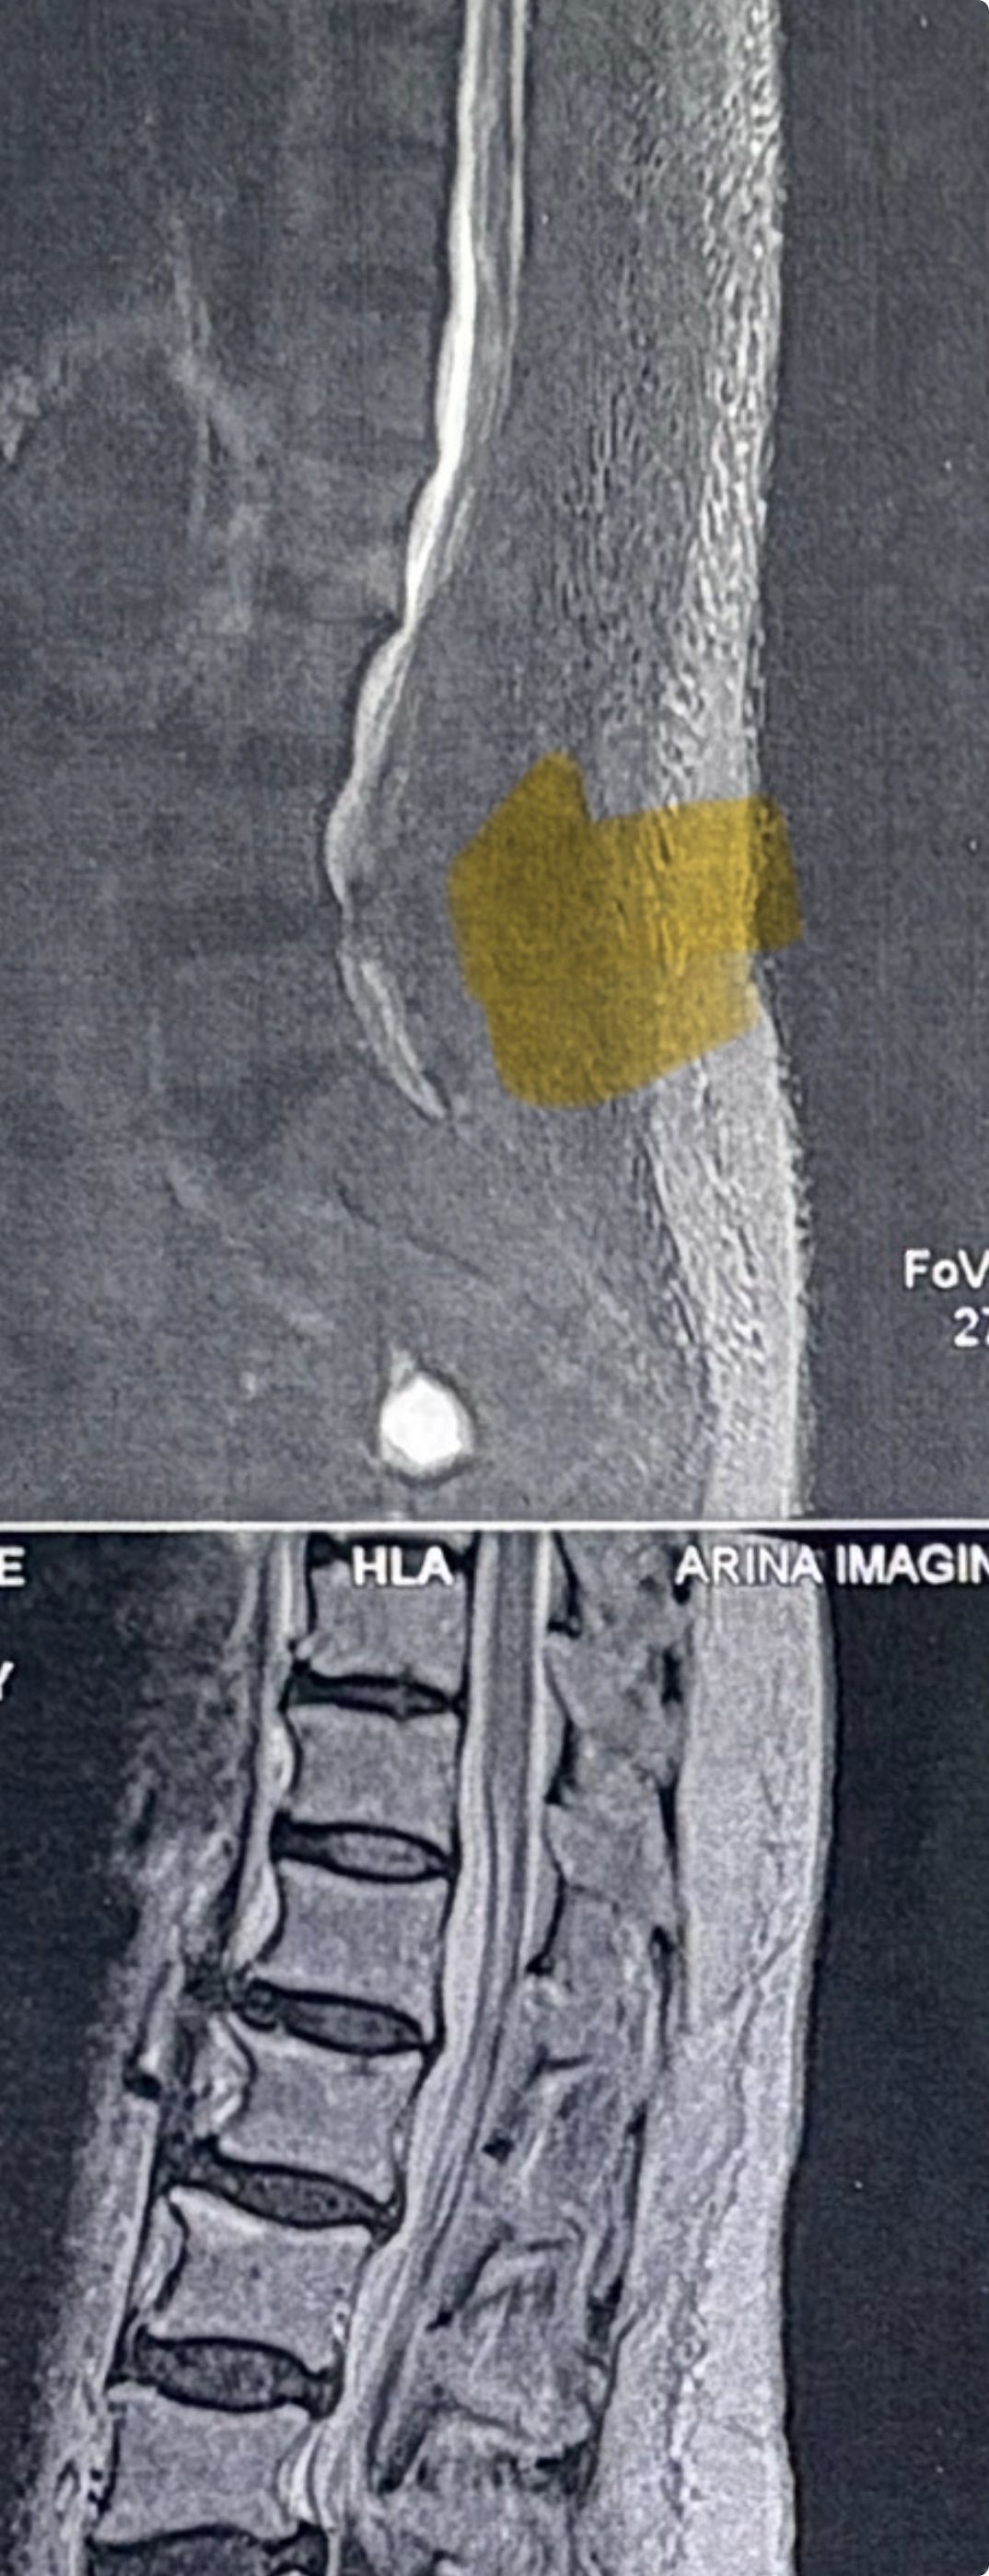

41 years old man presented to my clinic in October 2023 with acute and sever R neck pain with radicular pain to his R upper extremity along C6 dematom since 2 weeks ago. Examination didn’t show any upper motor signs. Was suggested urgent surgery

I ordered EMG/ NCV : showed mild R C6, C7 irritation without any active axonal loss

In his MRI was reported R. para R. IVF Massive extrusion. I decided to control his pain and manage this patient with reevaluation of patient every other session. For 5 sessions i just used acupuncture and laser and IFC and mild adjustments to his R. T3-T7 and mild arthosteem to above and below involved segment. Cervical adjustment considered contraindicated for this patient. From session 6th- 8th i started to use mild/gentle cervical decompression. He used soft cervical collar all the time. His pain decreased by 80 percent

I gave him cervical traction pump to be used 3-5 times per day at home for the next 3 months and i released the patient. He was evaluated every week once for one month and after that every 2 weeks. After 3 month I repeated MRI. Size of the herniated disc was reduced greater than 50 percent. Asked him to do another mri in 6 months

In general: Precise selection of the patients, examination,diagnosis, plan of management, reevaluation and treatment can be done by doctors of chiropractic for the patients with spinal disc herniation and stenosis Moreover giving reasonable time to these kind of patients under direct supervision by their chiropractic doctors can prevent unnecessary surgery. Proper selection of these kind of patients is another important fact that can be done precisely by chiropractors.

MRIs before and after proper management of this patient: